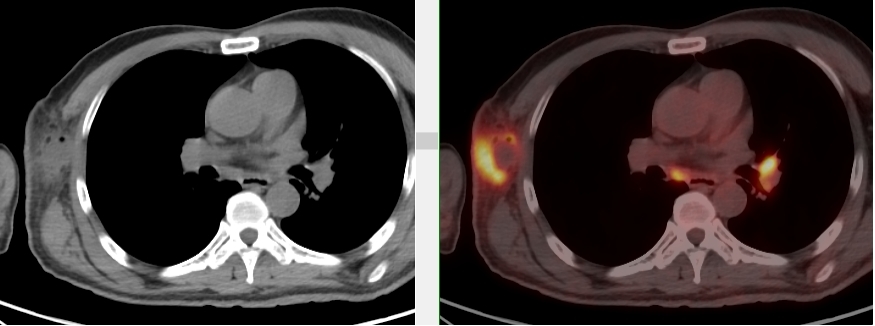

完善胸部強化CT考慮縱隔MT并縱隔、右腋窩及雙肺門多發腫大淋巴結,后行超聲引導下行右腋窩腫物穿刺活檢術,病理首先考慮惡性腫瘤,因穿刺組織局限,腫瘤細胞成分過少,不能明確診斷。

完善PET/CT檢查示:右側腋窩、雙側中下頸部、縱隔、雙側肺門多發MT,建議淋巴結活檢。后患者行右腋窩淋巴結切除活檢術,經北京大學第三醫院病理科會診示:右腋窩淋巴結惡性腫瘤,呈淋巴竇內生長模式,瘤細胞呈上皮樣,異型性明顯,伴中性粒細胞浸潤。結合病史及免疫組化,考慮為SMARCA4(BRG1)缺失的胸部腫瘤,伴神經內分泌標記表達。

胸部SMARCA4缺失腫瘤好發部位為縱隔、肺、胸膜,多呈侵襲性生長,普遍發生轉移,累及骨、肺、腦、腎上腺等,預后較差。

本例為罕見病理類型的腫瘤,影像學表現無明顯特異性,診斷困難。強化CT和穿刺病理已基本明確為惡性腫瘤,行PET/CT檢查一是為了全身檢查,完善分期,二是根據PET代謝情況指導進行生物靶區活檢,進一步明確病理診斷。最終,PET/CT除縱隔病變外發現更多頸胸部淋巴結代謝異常,綜合考慮后對腋窩淋巴結進行切除活檢,最終得到病理證實。